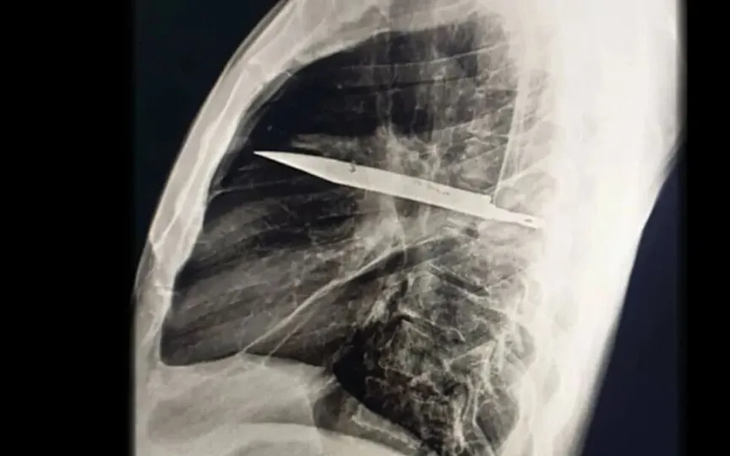

Phim chụp X-quang ngực của bệnh nhân cho thấy một lưỡi dao lớn găm vào giữa lồng ngực

Khi thăm khám, bác sĩ nhận thấy ngực phải của bệnh nhân không nở ra đầy đủ khi hít vào, kèm theo lỗ rò rỉ dịch mủ có mùi hôi. Kết quả chụp X-quang khiến toàn bộ ê-kíp choáng váng: một lưỡi dao lớn gãy nằm gọn trong khoang ngực, kéo dài từ vùng xương bả vai phải đến trước xương sườn.

Hình ảnh chụp CT cho thấy, mảnh dao đã chui vào giữa khe xương sườn số 5 và 6 từ phía sau, rồi mắc kẹt, đầu nhọn dừng lại ở phía trước giữa xương sườn số 3 và 4. Xung quanh mảnh kim loại, các mô cơ thể đã hình thành bao xơ, giống như cơ chế tự vệ của hệ miễn dịch để “cô lập” dị vật, ngăn ngừa tổn thương lan rộng. Đây chính là lý do bệnh nhân không hề biết trong lồng ngực mình có cả một lưỡi dao suốt ngần ấy năm.